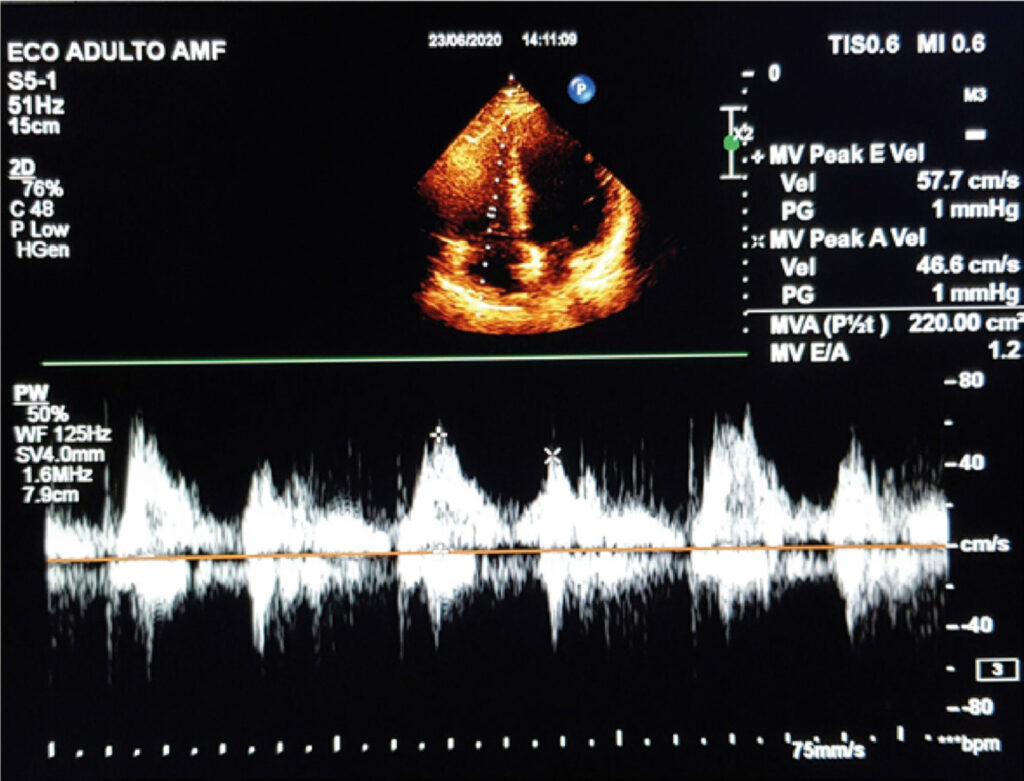

This observational cross-sectional study included a total of 97 patients (56 women) aged 61.5 ± 12.5 years. The assessed parameters included RV E/A ratio; peak E-wave and A-wave velocity, E-wave acceleration and deceleration time, and integral E-wave and A-wave velocity-time; and pulmonary artery systolic pressure (PASP), tricuspid reflux velocity, inferior vena cava diameter, and right atrial volume.